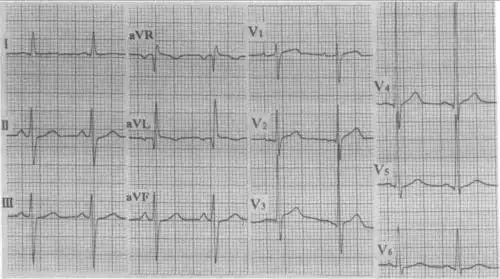

图21-9 左前分支阻滞